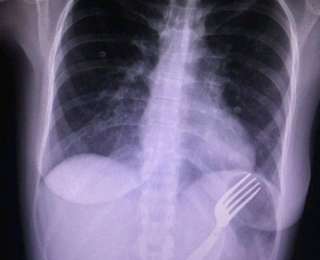

Коллекция рентгеновских снимков с обнаруженными внутри пациентов предметами пополнилась еще одним. Так, врач из Курска разместил в своем твиттере фото вилки, неизвестно каким образом оказавшейся во внутренностях женщины.